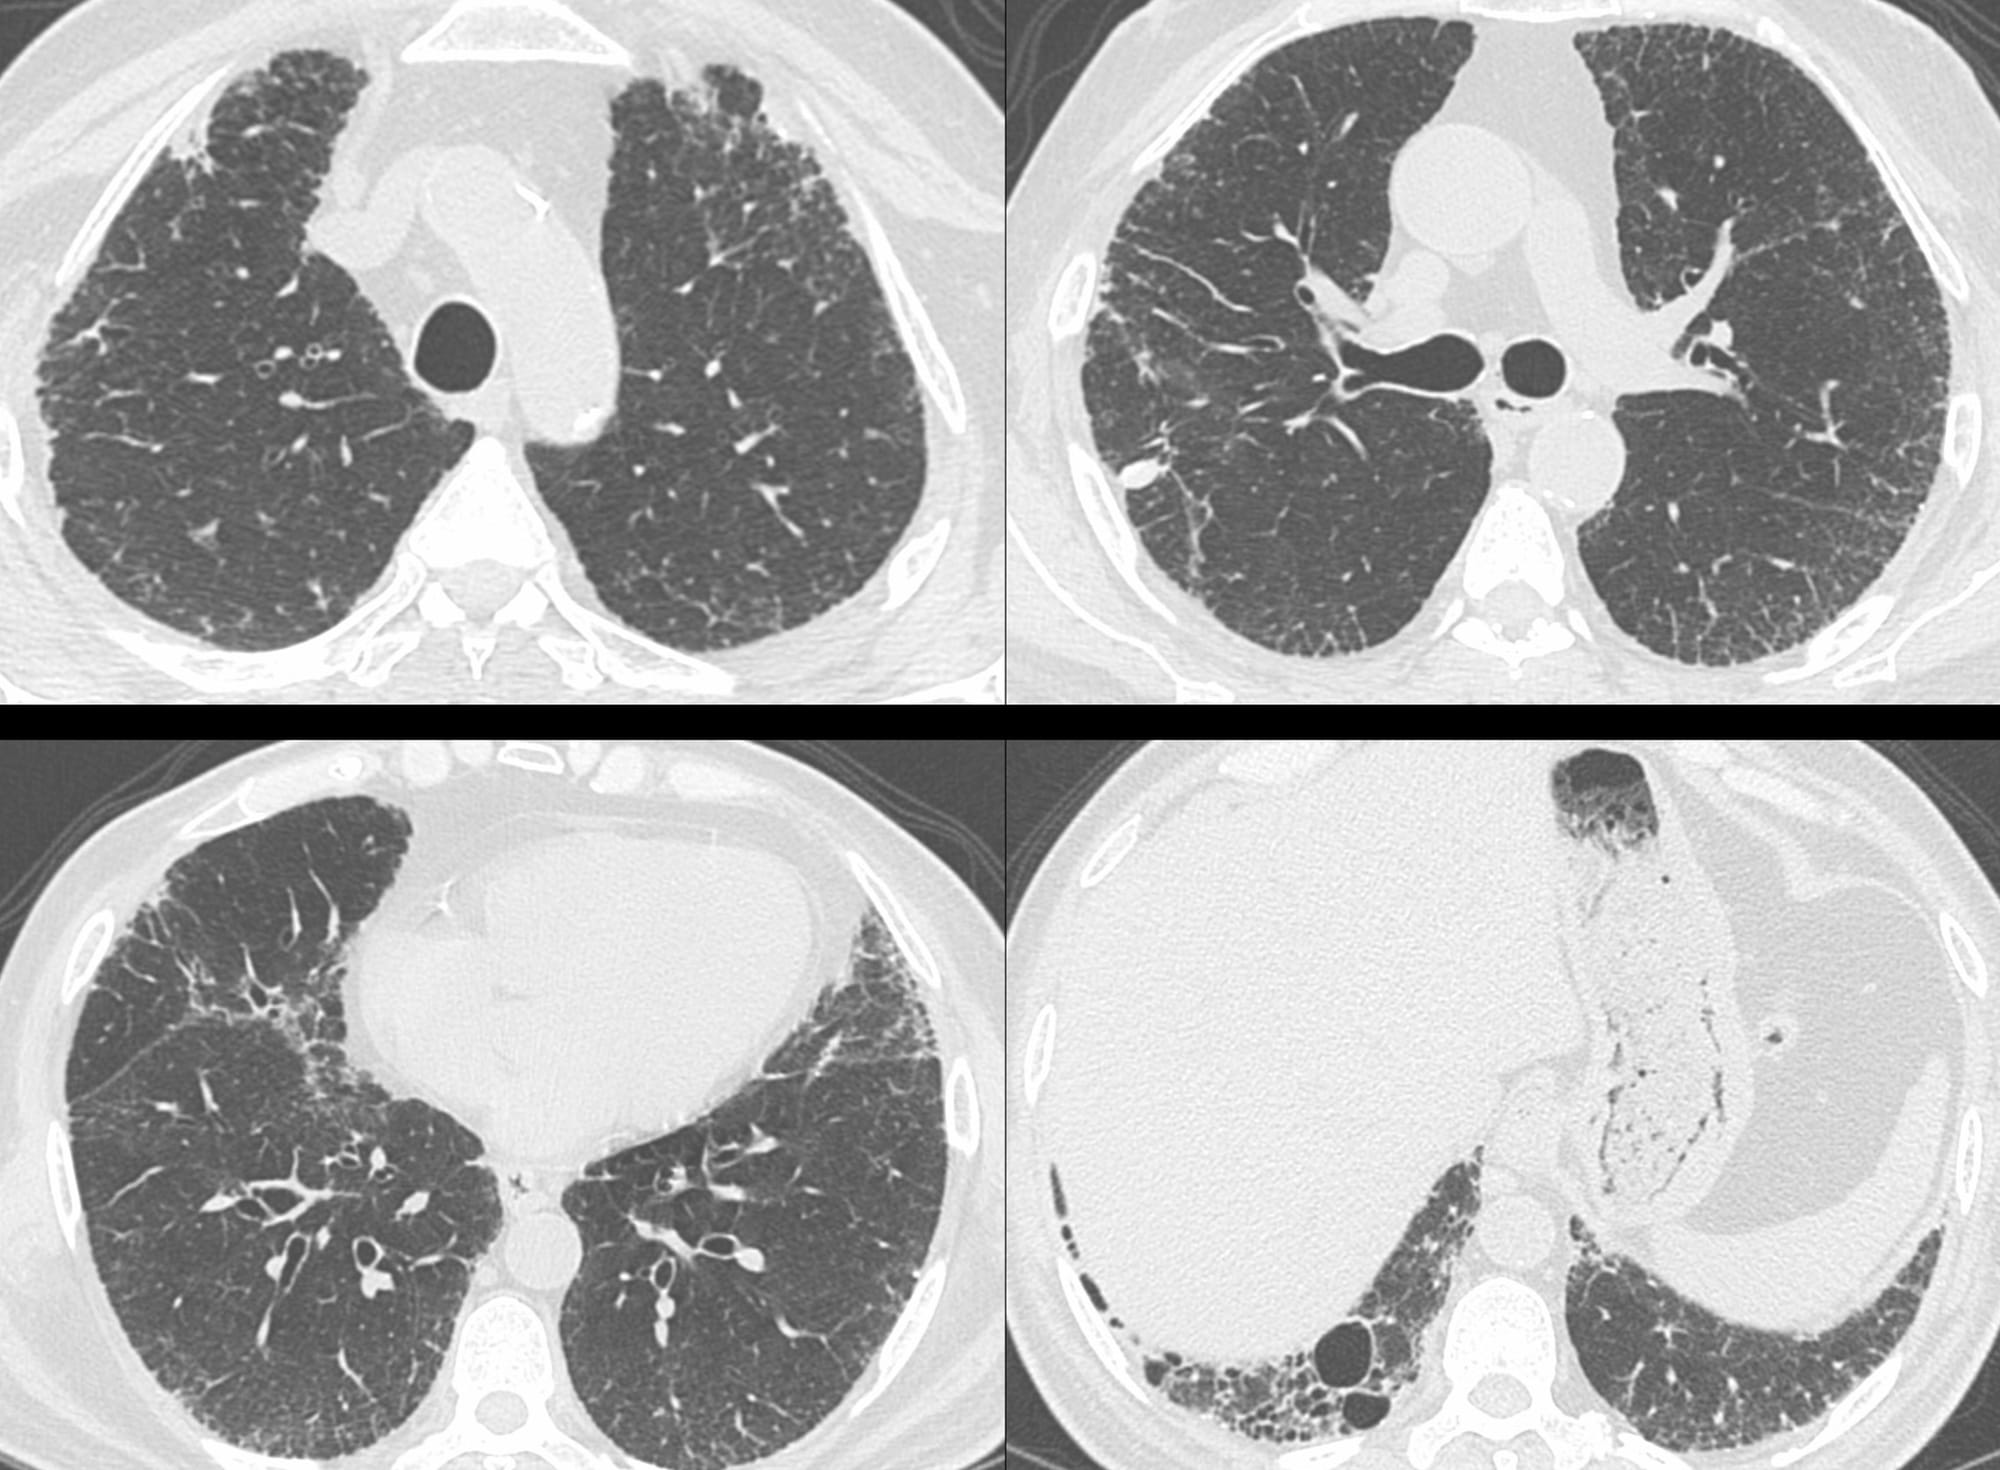

8 years later, his elder brother presented with mild breathlessness and a CT scan shows a typical UIP pattern.